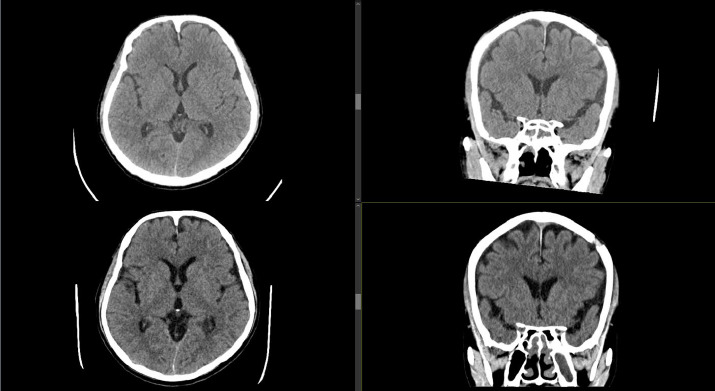

迟发性慢性硬膜下血肿(cSDH)是外伤性脑损伤(TBI)后常见但潜在严重的并发症。轻度脑外伤通常由初级保健提供者(pcp)管理,特别是在像马来西亚这样资源有限的大国家,三级神经外科服务可能会延迟。早期识别危险体征和症状并及时转诊对于防止临床恶化至关重要。我们描述的情况下,66岁的男子谁持续轻度头部损伤后,血管迷走神经性晕厥。他最初的脑部CT显示左侧中央前沟有一个小的外伤性蛛网膜下腔出血,24小时后的间隔扫描解决了这个问题。他没有随访就出院回家了。11周后,他出现双侧下肢无力和步态不稳,这促使他的全科医生紧急转诊。重复CT显示双侧急慢性硬脑膜下血肿,肿块效应需要紧急钻孔引流。患者术后表现良好,第4天出院,后续随访无临床或影像学复发。该病例强调了轻度TBI患者延迟cSDH的风险,即使在那些出院时CT扫描正常的患者中也是如此。pcp在识别高危患者、确保有组织的随访和促进及时的专科转诊方面发挥着关键作用。我们提倡更新马来西亚的头部损伤指南,以国际标准为模型,纳入高危患者的常规随访方案。

Delayed chronic subdural haematoma (cSDH) is a common but potentially serious complication following traumatic brain injury (TBI). Mild TBIs are commonly managed by primary care providers (PCPs), particularly in large, resource-limited settings such as Malaysia, where access to tertiary neurosurgical services may be delayed. Early identification of red-flag signs and symptoms and timely referrals are crucial to prevent clinical deterioration. We describe the case of a 66-year-old man who sustained mild head injury following a vasovagal syncope. His initial brain CT revealed evidence of a small traumatic subarachnoid haemorrhage over the left precentral sulcus, with resolution on an interval scan 24 hours later. He was discharged home without follow-up. Eleven weeks later, he developed bilateral lower-limb weakness and unsteady gait, which prompted an urgent referral by his general practitioner. Repeat CT revealed bilateral acute-on-chronic subdural haematomas, with mass effect requiring emergency burr-hole drainage. The patient showed excellent post-operative improvement and was discharged home on day 4, with no clinical or radiological recurrence on subsequent follow-up. This case highlights the risk of delayed cSDH in patients following mild TBI, even in those discharged with a normal CT scan. PCPs play a pivotal role in recognising high-risk patients, ensuring structured follow-up and facilitating timely specialist referral. We advocate for updating the Malaysian head injury guidelines to incorporate routine follow-up protocols for at-risk patients, modelled after international standards.